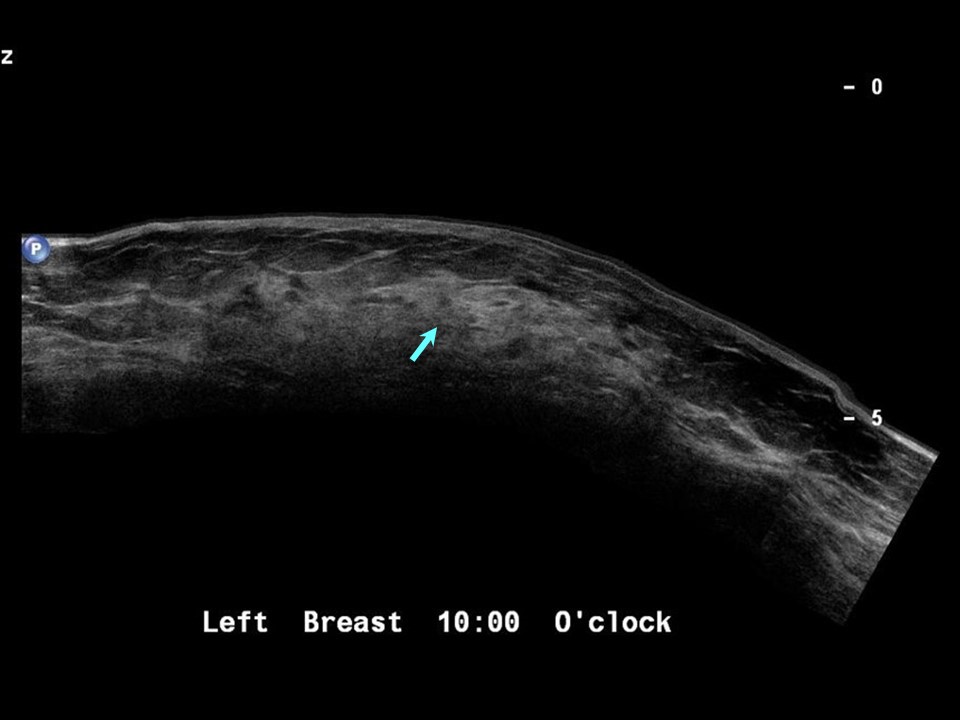

From screening.iarc.fr

Atlas of breast cancer early detection What Does Echotexture Mean Various conditions lead to coarse. The appearance can be normal or heterogeneous due to some myometrial pathology, for. Coarse echotexture, marked by increased sound scattering, indicates underlying liver disease. It can be caused by inflammation, fibrosis, cysts, tumors, or scarring, and. What are the possible causes? This refers to the brightness of the tissue. A fine or homogeneous echotexture indicates. What Does Echotexture Mean.

Atlas of breast cancer early detection What Does Echotexture Mean What does it mean to have an ‘echogenic liver’? The appearance can be normal or heterogeneous due to some myometrial pathology, for. Morrey's the elbow and its. Echotexture refers to the visual representation of the liver’s ultrasound image. It can be caused by inflammation, fibrosis, cysts, tumors, or scarring, and. This refers to the brightness of the tissue. Various conditions. What Does Echotexture Mean.